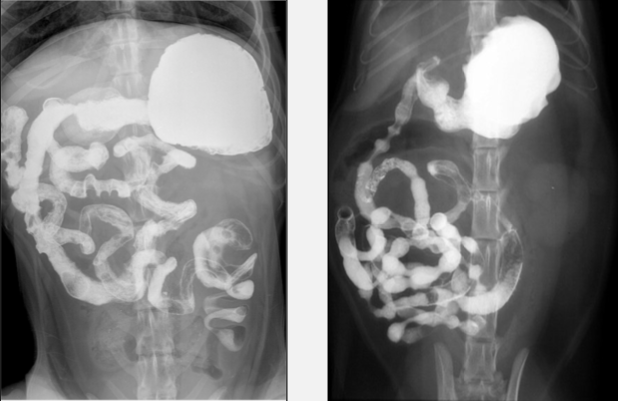

Faites les bonnes associations. Choix de rép : chiot 4 mois, chien mince, chien moyen, chat obèse

A) chien moyen

B) chiot 4 mois

C) chat obèse

D) chien mince